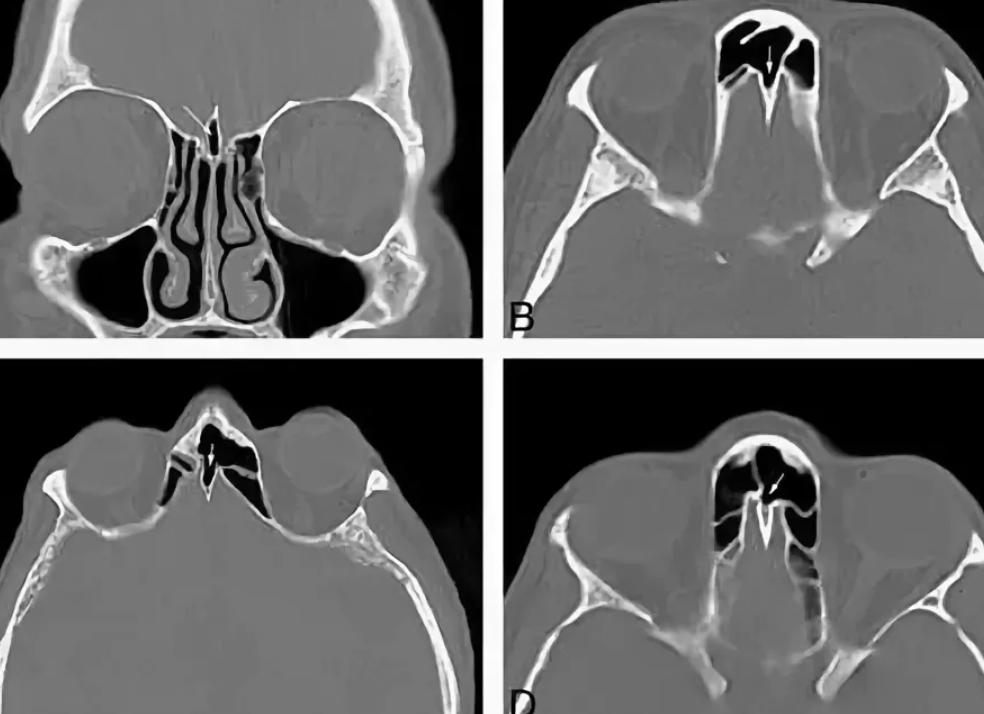

Наиболее современный метод диагностического обследования, который, в свою очередь, позволяет получить наиболее достоверную информацию не только о строении, но и о полной работе органа – МРТ. При помощи этого метода диагностического обследования, можно выявить нарушения не только в печени, но и в иных органах, например: мочевом пузыре, жёлчном пузыре, 12-перстной кишке и т.д.